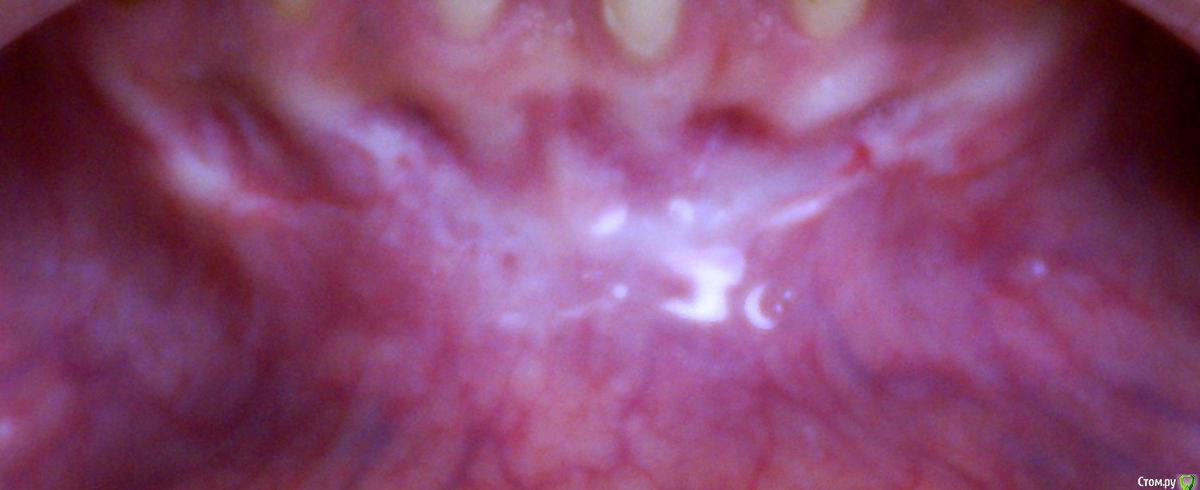

Irina_S Опубликовано 15 июня, 2017 Поделиться Опубликовано 15 июня, 2017 Здравствуйте, уважаемые специалисты! Заранее прошу прощения за не слишком качественные фото! Почти восемь месяцев назад мне была сделана вестибулопластика на нижней челюсти.За пять дней до операции ситуация во рту выглядела так: Для проведения операции были такие показания: Вот ещё описание самой операции, которая была 24 октября 2016 г.: Через шесть дней после операции: Ещё через шесть дней, 5 ноября: Прошла ещё неделя, 12 ноября: Следующий раз фото, к сожалению делалось через три с лишним недели, 4 декабря, в разных ракурсах: После этого визуальные изменения касались только уменьшения белёсых мест от разреза.Вот состояние на 10 июня этого года с разными вариантами оттягивания губы: По результатам заживления я не вижу разницы в глубине преддверия, ради чего и проводилась операция.К тому же всё время с момента операции присутствуют стягивающие ощущения и ощущение инородного тела в подбородке. Ответьте, пожалуйста, правильно ли была сделана операция вестибулопластики?Спасибо за внимание! Ссылка на комментарий

Irina_S Опубликовано 16 июня, 2017 Автор Поделиться Опубликовано 16 июня, 2017 у Вас образовались тяжи в области клыков,которых раньше не было. А можно Вас попросить уточнить, что Вы называете тяжами?Под номером 1, под номером 2 или и то и другое вместе? Ещё вот такая хронология: 24 октября была сделана вестибулопластика, 28-го сняли швы, до 13 ноября я касалась кончиком языка "кармана" в глубине линии разреза, отметила это на фото, чтобы было понятно, о чём речь. 14 ноября проводилась обработка зубов с помощью аппарата Вектор и были заложены саморассасывающиеся лечебные повязки на обе челюсти, в том числе и в этот "карман". В этот день увидела, что "карман" визуально склеился из-за заложенной повязки, и я перестала на несколько дней делать упражнения с надуванием губ и касанием кончиком языка.А потом этот "карман" исчез и в итоге получилась поверхность, обозначенная на первой картинке под номером 3. Вопрос: мне не надо было допускать срастания двух поверхностей слизистой, чтобы этот "карман" остался, или его исчезновение и должно было произойти в процессе заживления? (думаю, что это срастание и вызвало ощущение стягивания и уплотнения внутри подбородка в виде инородного тела) Ссылка на комментарий